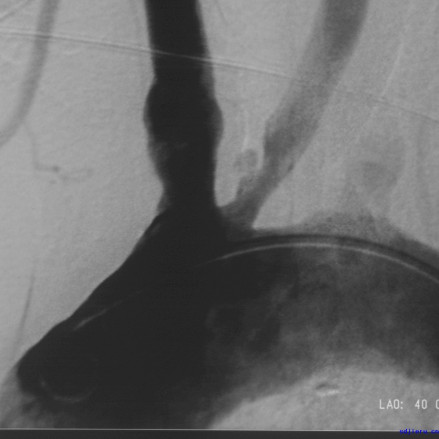

脑血管造影或多普勒证实有颅内动脉狭窄者,药物治疗无效时,可考虑手术治疗。